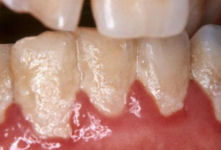

Η Οδοντική Πλάκα είναι ένα σχεδόν αόρατο στρώμα μικροβίων που αναπτύσσεται πάνω στα δόντια και τα ούλα και ιδιαίτερα στα σημεία ανάμεσα στα δόντια, αλλά και κατά μήκος της γραμμής των ούλων. Είναι μια μαλακή, σχεδόν άχρωμη ή υποκίτρινη μάζα μικροβίων που αποτελούν την φυσιολογική χλωρίδα του στόματος, που όμως αν αφεθούν χωρίς απομάκρυνση (βούρτσισμα- οδοντικό νήμα), προκαλούν διάφορες νόσους και φλεγμονές όπως τερηδόνα, ουλίτιδα και περιοδοντίτιδα.

- Υπερ-ουλική πλάκα: Αναπτύσσεται πάνω στα ούλα και στο εμφανές τμήμα του δοντιού (μύλη).

Αμέσως μετά το βούρτσισμα, η μικροβιακή πλάκα θα αρχίσει να σχηματίζεται ξανά . Αρχικά, η επιφάνεια των δοντιών καλύπτεται από ένα πολύ λεπτό στρώμα πρωτεϊνών πάνω στο οποίο αρχίζουν να προσκολλώνται σιγά σιγά διάφορα βακτήρια και να δημιουργούν έτσι τη μικροβιακή πλάκα